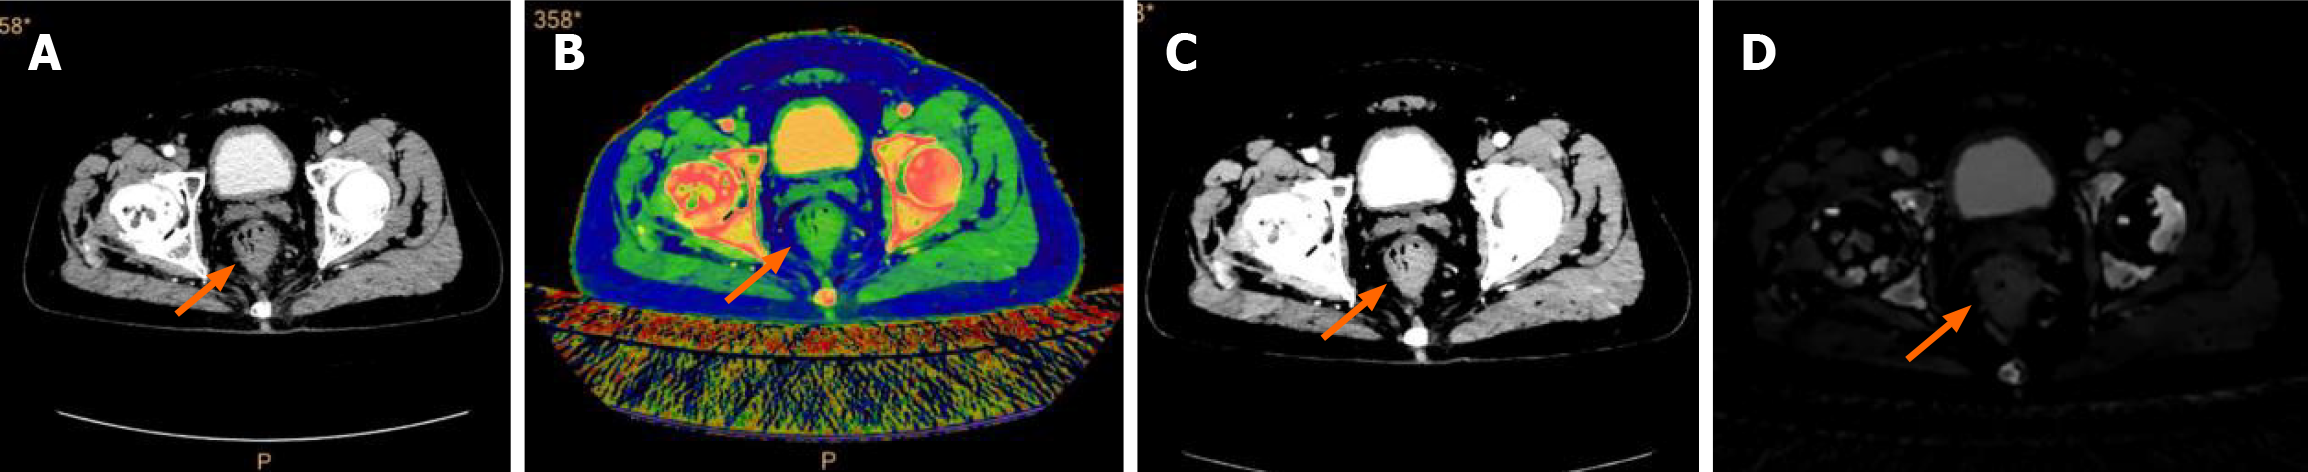

DLCT example images of a 57-year-old male CRC patient are shown in Figure 3. Spectral cleansing based on DLCT can reduce electronically tagged stool cleansing artifacts in CT colonography (CTC)[26]. A study showed that VMIs generated from DLCT significantly improved CTC image quality and enhanced the effectiveness of electronically cleansing[27]. This approach overcomes the challenges associated with onerous bowel preparation for colon cancer screening and poor tolerance of patients to colon examination to some extent.

Figure 3

Figure 3 Colorectal cancer and dual-layer spectral computed tomography images. A: Conventional computed tomography image in the arterial phase (AP); B: Effective atomic number in the AP; C: Virtual monochromatic image; D: Iodine concentration in the AP.